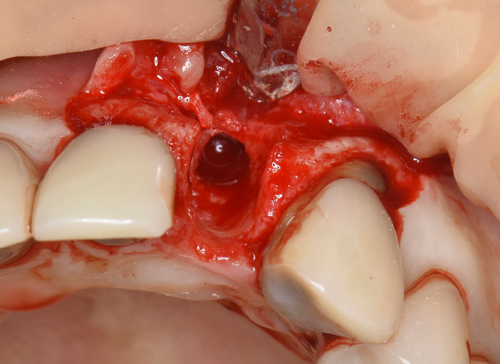

抜歯した歯根の先端には肉塊の腫瘍が一緒に付着していました。どんどん骨が溶けていく根源です。

腫瘍摘出ドリルで骨に付着している肉塊を徹底的にはく離させます。

唇側の半分がほとんど骨が失われていました。この状態からインプラントを移植して、不足している骨も同時に再生定着

させていきます。